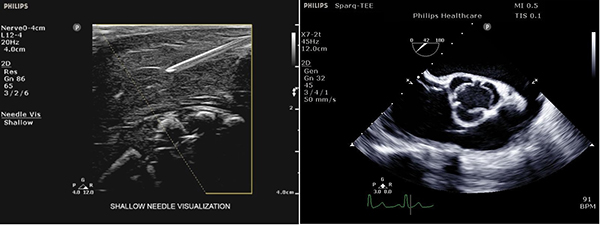

穿刺の針の可視化を強化するNeedleVisualization機能,高分解能のTEEトランスジューサなど,円滑にエコー観察をするための機能を搭載可能です。